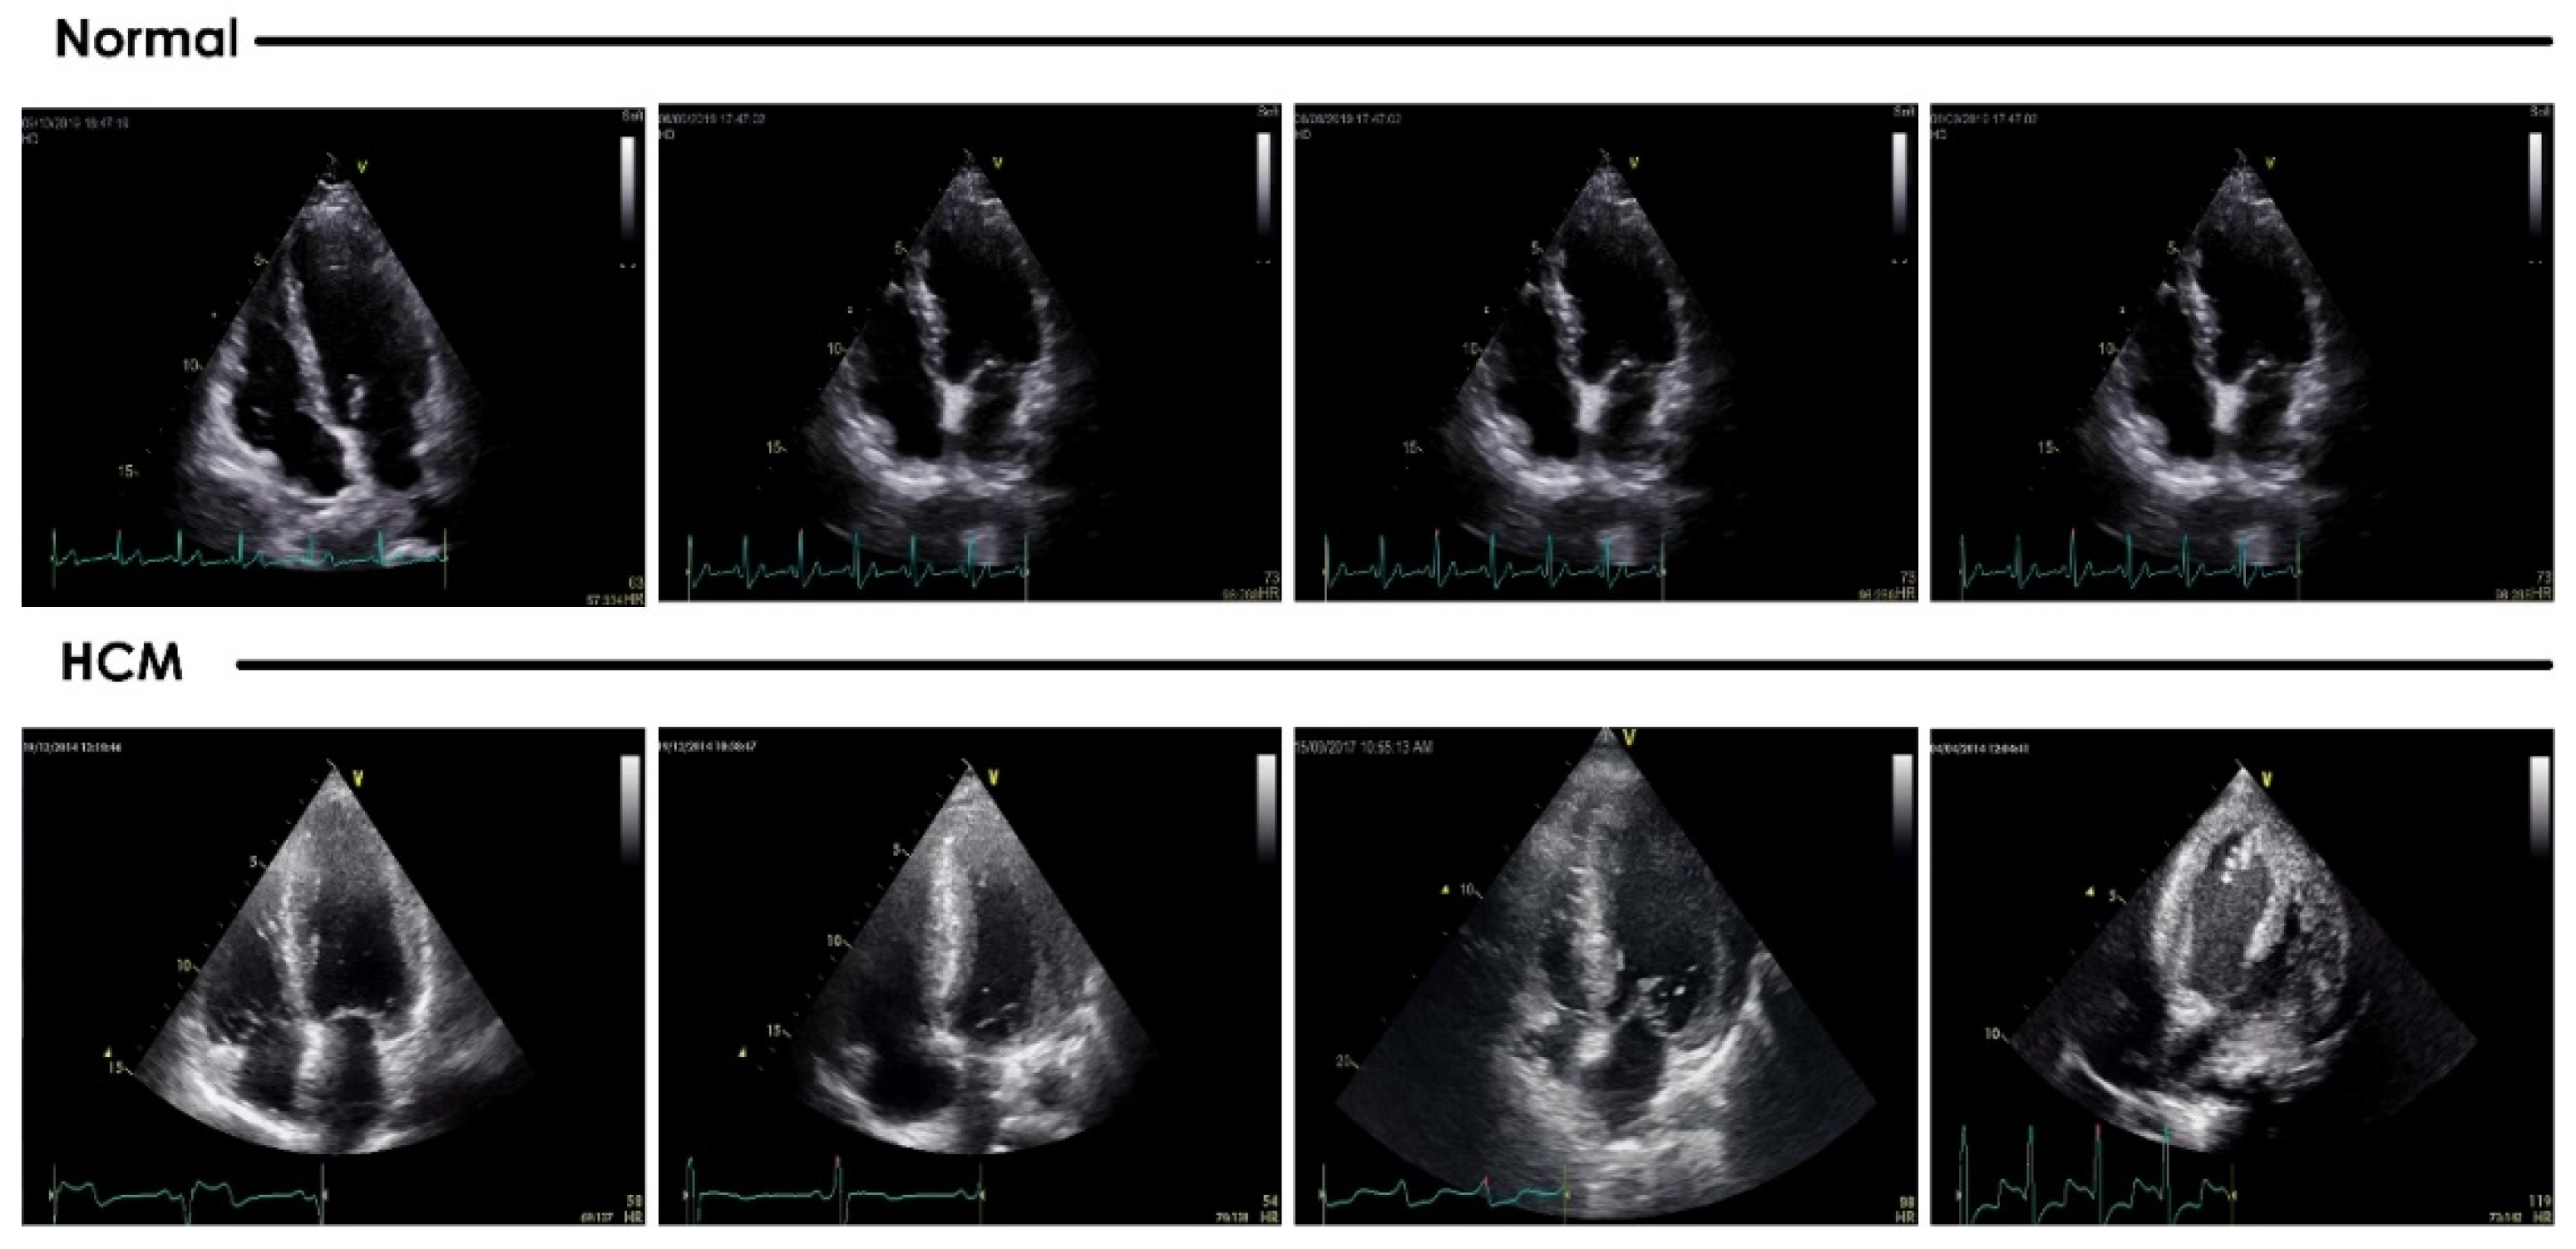

2. Materials

3.1. Preprocessing